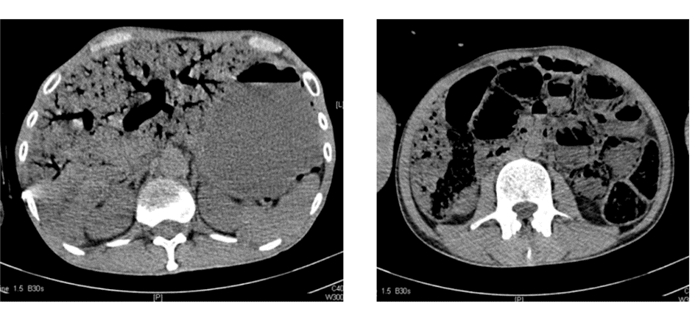

患者男性,46岁。突发持续性腹痛2 d加重6 h,伴恶心、腹胀、气急、气促。既往否认高血压、糖尿病、腹部手术史。发病前1个月患者食纳差,近3 d只进食饮料。初就诊于社区门诊,后因腹痛加重,急诊转入我院。查体:T 36.4 ℃,P 132次/min,BP 104/71 mmHg(1 mmHg=0.133 kPa),SPO2 100%。急性病容,精神萎靡,库斯莫尔呼吸,皮肤巩膜未见黄染,腹部稍膨隆,全腹压痛、反跳痛及腹肌紧张,腹部移动性浊音阴性,肠鸣音消失。实验室检查:血常规 白细胞 14.42×109 L-1,中性粒细胞94.7%;血气分析 pH 7.08,二氧化碳分压12.0 mmHg,氧分压170.0 mmHg,乳酸 8.4 mmol/L,实际碳酸氢盐3.6 mmol/L,标准碳酸氢盐6.4 mmol/L,剩余碱(B)-23.8 mmol/L;尿常规 比重1.010,葡萄糖14.0 mmol/L,酮体4.0 mmol/L;生化 谷丙转氨酶 31 U/L,谷草转氨酶 37 U/L,尿素氮12.9 mmol/L,肌酐193 μmol/L,葡萄糖55.6 mmol/L,二氧化碳 5.2mmol/L,钾4.2 mmol/L,钠142.2 mmol/L,钙2.48 mmol/L;血淀粉酶57 U/L。影像学检查:腹部CT提示肝内门脉系统明显积气扩张,积气形态沿门脉分支分布,门脉腹腔内分支也见积气扩张影像。肠腔积气、扩张,局部肠壁间可见多发气泡影像,肠壁坏死可能(图 1)。诊疗经过:给予患者液体复苏、控制血糖、纠正酸中毒、保留导尿、胃肠减压等治疗,并完善术前准备。入院1.5 h后患者突发血压下降,后经积极抢救无效,患者于入院2.5 h后死亡。

| 图 1 患者腹部CT结果 |